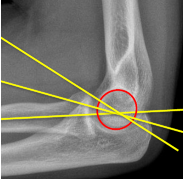

A: Radiocapitellar Line

assesses the alignment of the radius and capitellum. No average or range is specified.

Q what is the name of this measurement? and what is the average + range?

A: Anterior Humeral Line

assesses the alignment of the distal humerus. No average or range is specified.